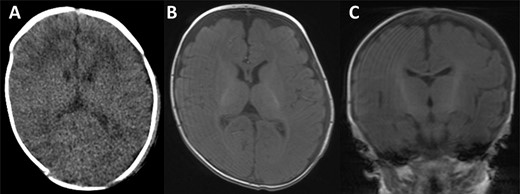

The collection was tapped, and pus was aspirated and sent for microscopy, culture and sensitivities. Gram negative rods were seen in the aspirate and a surgical evacuation was performed. A left parietal incision over the dome of the collection was performed, the pus evacuated and copious irrigation with warm Ringer’s solution and hydrogen peroxide was performed, followed by debridement of the space and underlying bony surface (Fig. 3). Escherichia coli was cultured from both pus and bone samples and S. epidermidis was cultured from the blood. Following the procedure, the patient improved with no further fevers and with a progressive decrease in CRP. He received 3 weeks of intravenous antibiotics followed by oral ciprofloxacin for a week. He was discharged home 20 days after surgery. Repeat CT and magnetic resonance imaging (MRI) of the head revealing no complications (Fig. 4).

CT scan and MRI taken of the patient upon discharge. In all images, a well-defined skull with no thinning is illustrated and with a resolved haematoma.